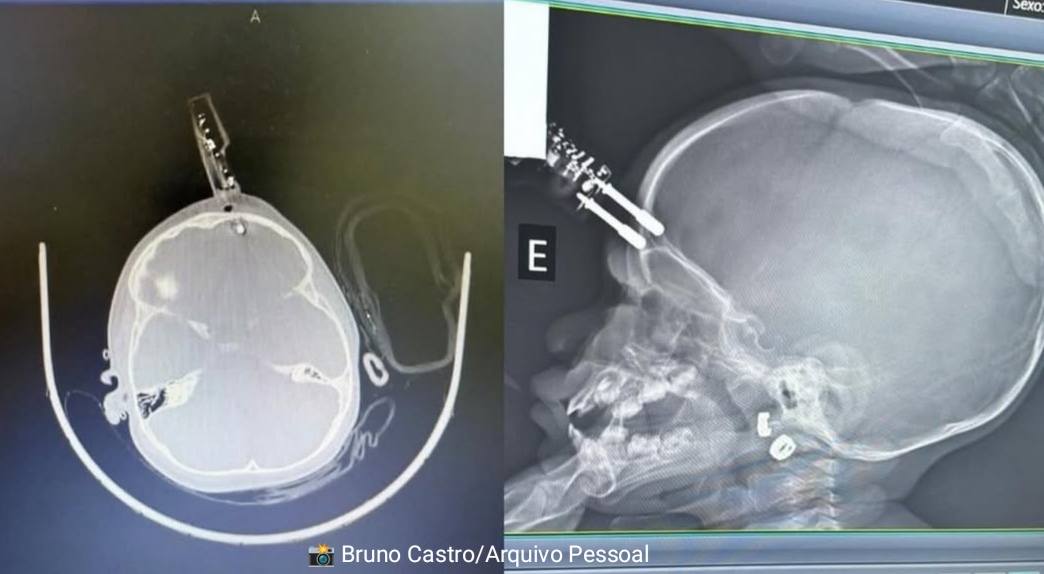

Uma bebê de 1 ano precisou ser submetida a uma cirurgia de urgência após um acidente doméstico registrado na terça-feira (13), em Divinópolis, no Centro-Oeste de Minas Gerais. A bebê caiu da cama e sofreu uma perfuração na cabeça causada por um carregador, que atingiu a região frontal do crânio, próximo ao olho.

A criança foi levada ao hospital e encaminhada diretamente ao centro cirúrgico, onde passou por procedimento para retirada do objeto e reconstrução da área lesionada. Ela permanece internada em observação e, segundo a equipe médica, não apresenta sinais de sequelas neurológicas até o momento.